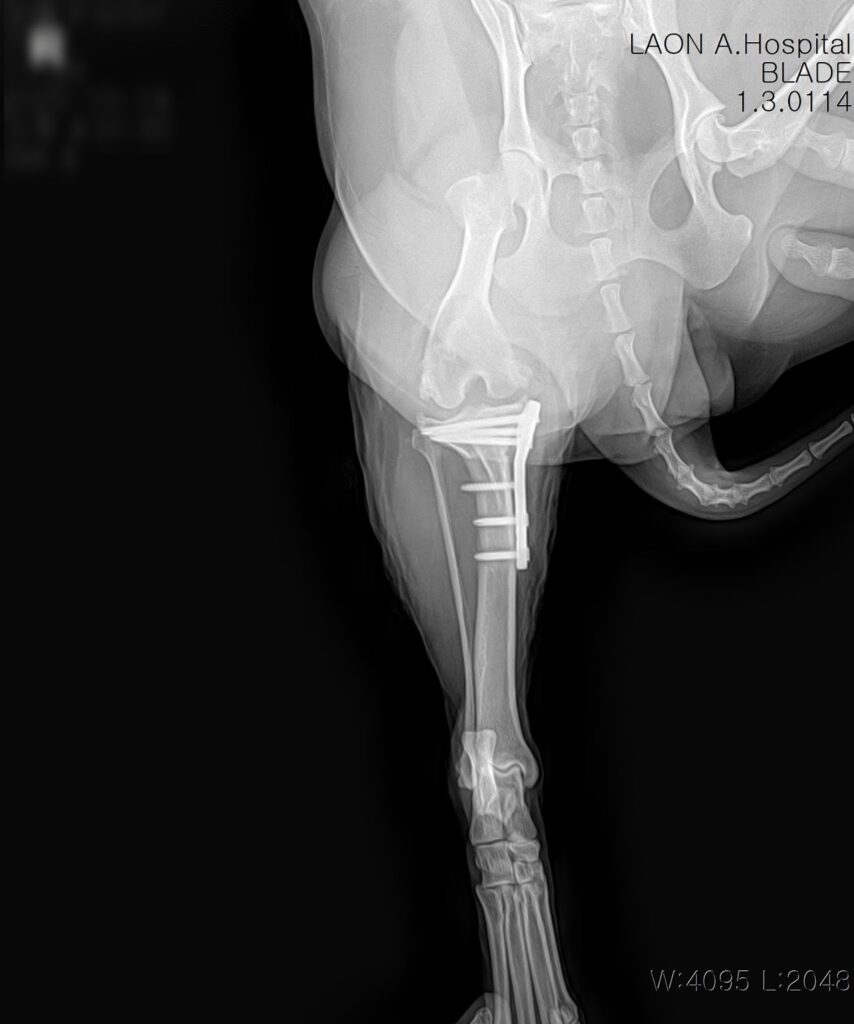

십자인대 단열 진단

방사선 촬영 결과, 우측 십자인대 완전 파열과 무릎 관절의 퇴행성 관절염 소견이 함께 확인되었습니다. 보행 시 무릎이 흔들리며 통증이 동반되는 상태로, 정상적인 활동을 위해 TPLO 수술이 필요했습니다.

💬 TPLO 수술은 경골의 경사각을 교정해 십자인대가 없는 상태에서도 무릎이 안정적으로 작용하도록 도와주는 수술법으로,중·대형견의 십자인대 단열 치료에 널리 사용됩니다.

특이 소견이 없음을 확인한 뒤, TPLO 수술이 시행되었습니다.

💬 라온동물메디컬센터에서는 정형외과 전용 시뮬레이션 프로그램을 사용하여 경골의 각도, 절골 범위, 나사 위치를 정밀 계산한 후 수술을 진행합니다.

수술 후 방사선 사진/ 출처: 라온동물메디컬센터

수술은 마취 안정 하에 무사히 완료되었고 절개 부위 봉합 후에는 감염 예방과 부기 완화를 위한 처치가 이어졌습니다.